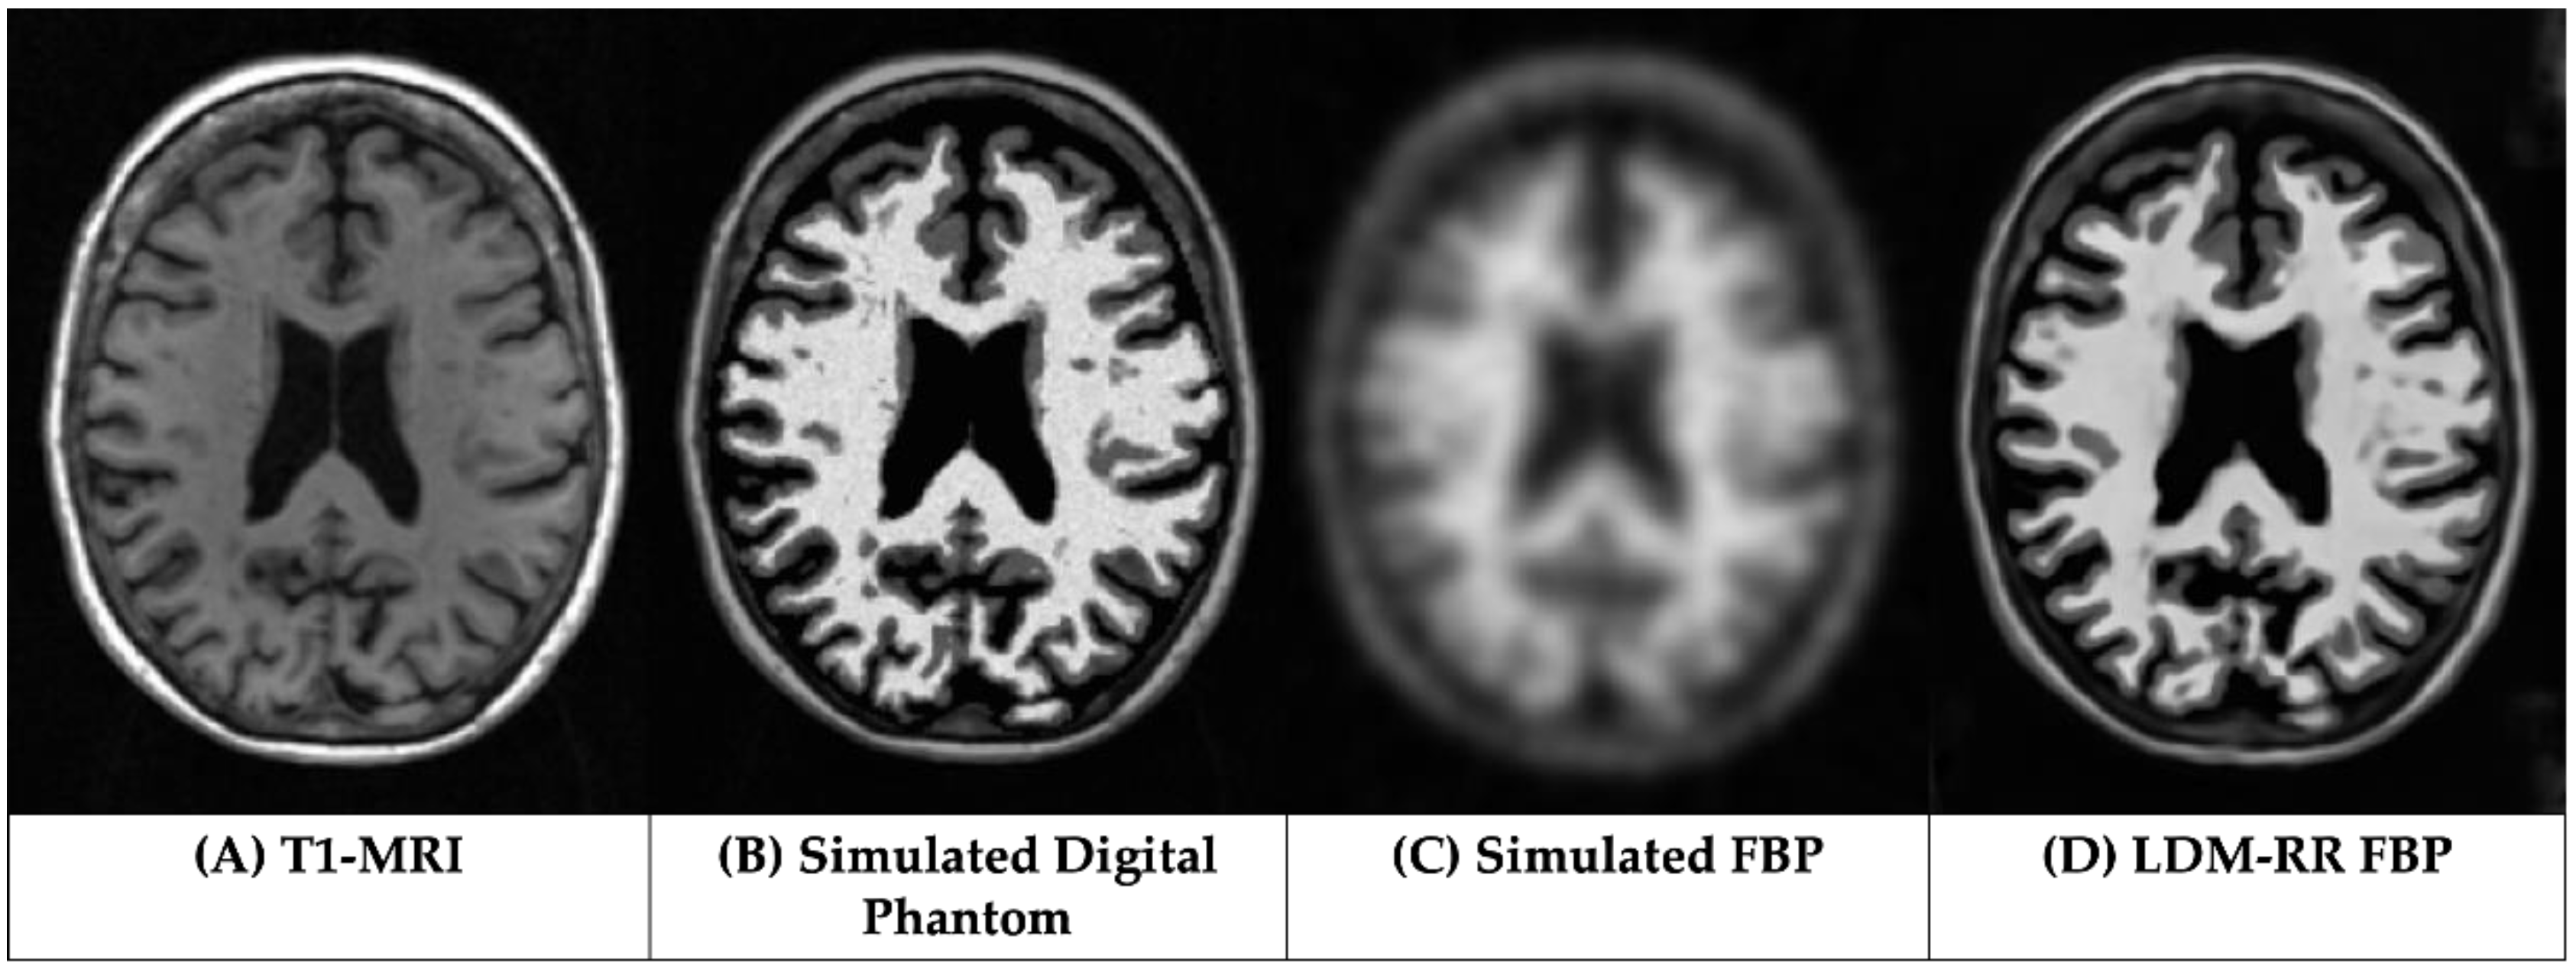

3.1. Qualitative Assessments